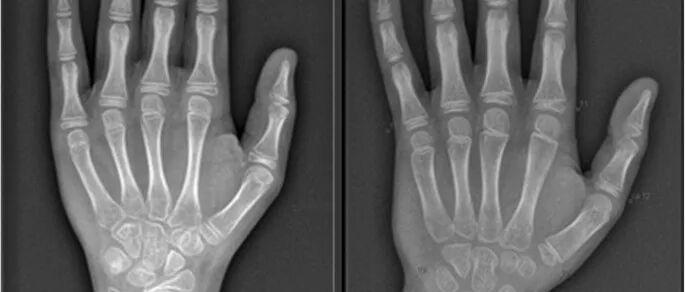

Bone age reflects the maturity of the skeleton and can assess an individual’s growth potential and the trend of sexual development maturity. Combining bone age can predict a child’s adult height through certain methods.

Bone age is influenced by various factors including gender, race, nutrition, health, environment, genetics, and developmental status. Although there are rules to follow, the range and variation are very large, and it is common for bone age to not completely match the actual age. For situations where bone age needs to be measured, you can refer to this popular science article👇: